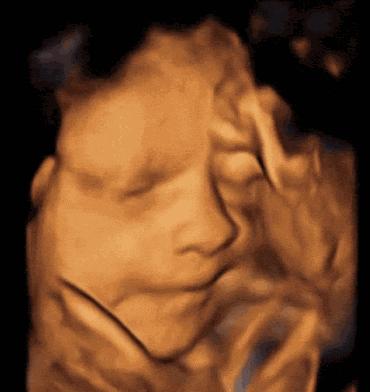

其实一般在怀孕22~26周,医生会安排准妈妈进行胎儿大排畸检查,主要通过三维或者四维彩超(两者选择其中一个即可)进行,可以说这是整个孕期最重要的检查项目之一。

虽然四维彩超已经是目前最先进的技术了,不仅可以检查胎儿的发育情况,还可以实时看到胎宝宝的各种动作,但这还是无法检查出胎儿所有的畸形,存在一定的局限性。